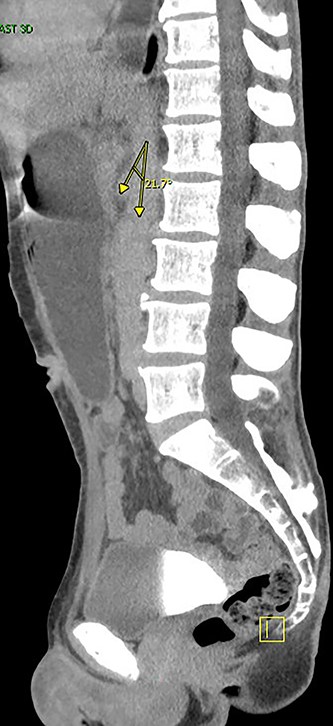

Two days later, the patient returned with emesis and poor oral intake. A repeat CT scan of the abdomen and pelvis with IV contrast was notable for increased fluid distention of the stomach and proximal duodenum with an abrupt transition at the level of the narrowed aortomesenteric interval. The aortomesenteric distance measured 5 mm with an SMA angle of 21 deg, confirming SMA syndrome (Figs 1 and 2). He was admitted, started on total parenteral nutrition (TPN). Preoperative endoscopy was performed revealing an area of constriction in the third part of duodenum. The duodenum was dilated without lesions or strictures; however, the endoscope could not traverse this area.

Angle between superior mesenteric and aorta artery measuring 21. deg.

The SMA originates from the aorta at the level of the L1 vertebral body, establishing an angle between the SMA and the aorta that ranges from 38 to 65 deg. Radiological findings are crucial in the diagnosis. Criteria include duodenal obstruction with rapid cutoff in the horizontal portion, aortomesenteric artery angle ≤25 deg, aortomesenteric distance ≤8 mm and abnormally high fixation of duodenum by the ligament of Treitz or low SMA origin [8, 9].